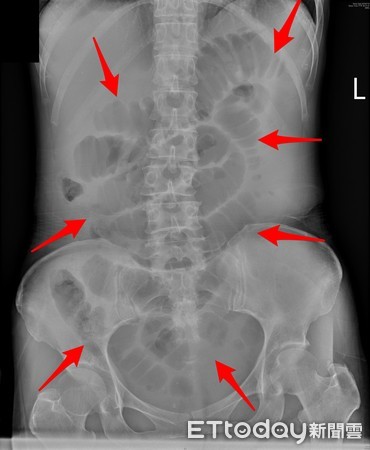

肝膽腸胃科醫師錢政弘指出,這名婦人就醫後,使用灌腸、瀉藥等方式,仍無法緩解腹脹情形。透過電腦斷層掃描,發現腸道已經被糞便塞住,腫成好幾倍大,幾乎占據了整個腹腔!患者透露,自己天天吃紫米飯配黑豆、南瓜、牛蒡等高纖食物,飲食習慣少油、少肉食。沒想到在攝取過多的膳食纖維情況下,糞便越來越硬,大便也大不太出來。

▲腹部X光紅圈處顯示,腸道已脹成好幾倍大。(圖/錢政弘醫師提供)